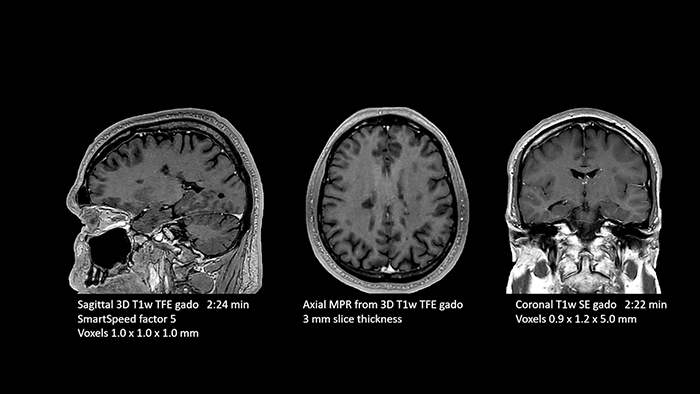

With SmartSpeed also scan times for diffusion imaging and motion-free imaging can be reduced. Scanned without contrast agent. Performed with 1.5T Ambition X, dS Torso coil.